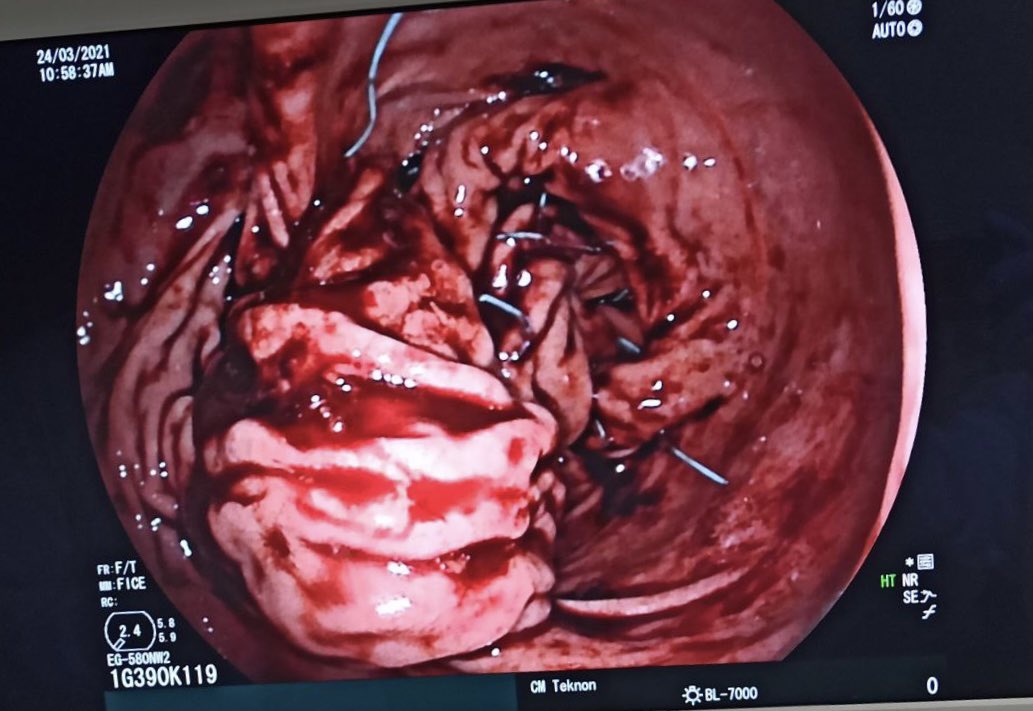

Laparoscopic Gastric Plication reparation with Endoscopic Plication with the @USGIMedical device. @EEndoscopia @Clinica_Teknon @SEEDendoscopia @secojoven @aec_obesidad @SociedadSeedo @Clinica_Teknon @EndoscopicTreat @sa6ater. Great work to all the team. 7%TBWL in 6 days.

Hoy hemos realizado por primera vez en Europa la reducción de hernia de hiato por endoscopia con #TIF con cierre de pilares quirúrgico. #endoscopia #cirugia @Clinica_Teknon @SEEDendoscopia #reflujo

Os enseñamos uno de los procedimientos endoscópicos que hacemos en nuestra unidad. POEM (Per Oral Endoscopic Myotomy) para el tratamiento de la Acalasia #achalasia #endoscopytreatment #centromedicoteknon